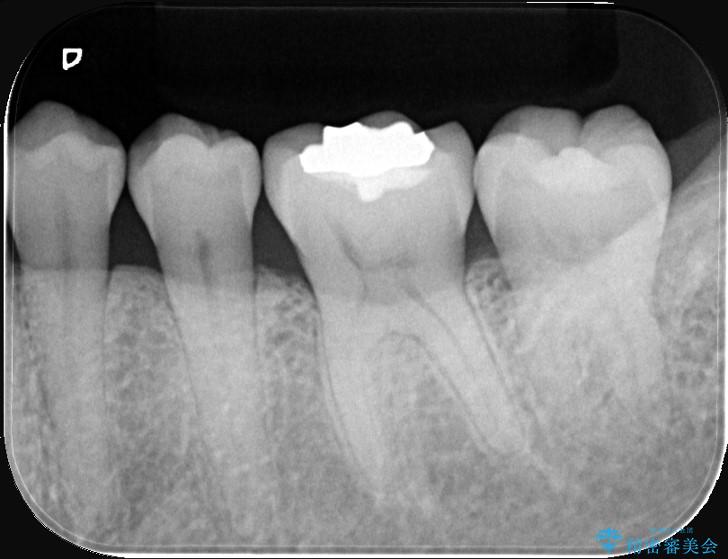

歯が欠けたことによるものか、もしくは以前装着された修復物の不適合が原因と考えられますが、銀歯(メタルインレー)と歯との間に大きな段差が認められ、汚れが溜まりやすい状態となっていました。

このような状態では、修復物の内部で虫歯が進行している可能性が高いため、治療が必要と判断しました。